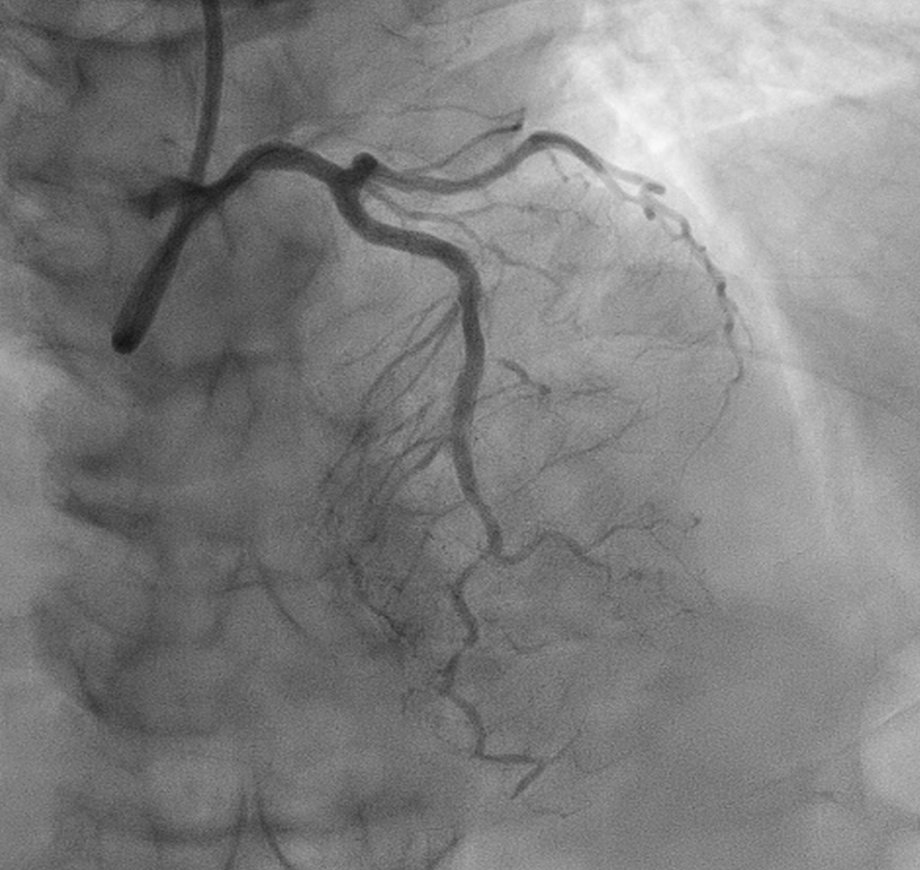

CORONARY ANGIOGRAM REVEALED CHRONIC TOTAL OCCLUSION AT THE MID LEFT ANTERIOR DESCENDING ARTERY (MLAD) WITH COLLATERALS FROM RIGHT CORONARY ARTERY. OTHER CORONARIES ARE NORMAL.

WE DECIDED TO INTERVENE THE CTO MLAD IN VIEW PERSISTENT ANGINA. BILATERAL RADIAL ARTERY PUNCTURE, WITH ANTEGRADE APPROACH. WE ENGAGED RIGHT CORONARY ARTERY WITH JR4 6 FR AND WIRED DOWN WITH RUNTHROUGH FLOPPY. ENGAGED THE LEFT CORONARY ARTERY WITH EBU 3.5 7FR. INITIALLY TRIED TO WIRE THE LAD WITH FINECROSS MICROCATHER (MC) USING SION BLACK WIRE BUT FAILED. SUBSEQUENTLY CHANGED TO GAIA 1ST AND MANAGED TO CROSS SUCCESSFULLY. IVUS SHOWED 360 DEGREE CALCIFICATION WITH 270 DEGREE CALCIFICATION MORE THAN 5 MM, IVUS CALCIUM SCORE 2. CALCIUM DEBULKING WAS DONE USING ROTABLATION WITH 1.5 BURR RUN 3 TIMES AT 220 KRPM FOR 10 SECS AND POLISHING RUN TWICE AT 140 KRPM. POST ROTA SHOWED PRESENCE OF FRACTURED CALCIUM WITH REVEBERATION SIGN. LESIONS WAS PREPARED FURTHER USING WOLVERINE 3.0 X 10MM AND 3.5 X 10MM. POST CUTTING BALLOON SHOT SHOWED NO DISSECTION, TIMI 3 FLOW AND RESIDUAL STENOSIS 30%. DECIDED FOR DCB WITH PANTERA LUX 3.0 X 20MM AND AGENT 3.50 X 30MM. FINAL SHOT SHOWED TIMI3 FLOW, NO DISSECTION SEEN. PATIENT REMAIN ASYMPTOMATIC AT 6 MONTHS AND REPEATED COROS SHOWED MODERATE STENOSIS AT MLAD WITH NEGATIVE FFR (0.92).